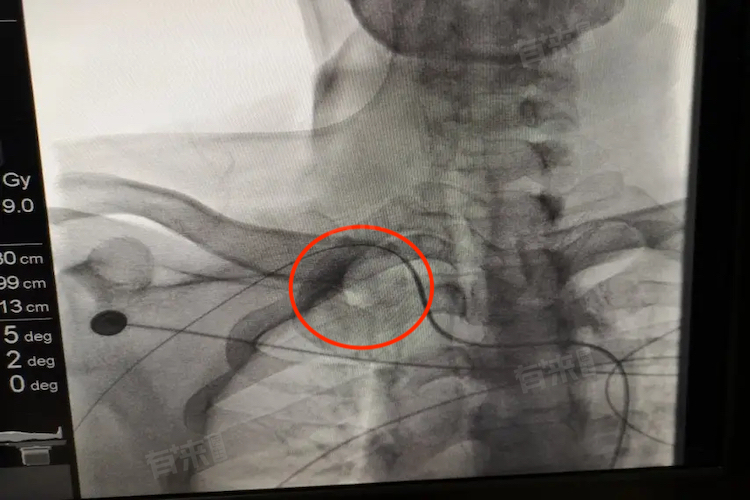

- 主动脉迂曲是指主动脉在解剖结构上出现的先天或后天性改变,导致其管腔出现曲折、延长的情况。这种改变可能由多种因素引起,包括高血压、高血脂、动脉瘤、动脉炎、动脉粥样硬化等血管疾病,以及环境污染、不良生活习惯等外部因素。主动脉迂曲不仅影响主动脉的正常形态,更可能对其功能产生不良影响,从而威胁患者的身体健康。

- 从病理生理角度来看,主动脉迂曲可能导致血流动力学改变,使得心脏负荷增加,心脏需要更加努力地工作以维持正常的血液循环。这种额外的负担可能导致心脏功能受损,进而引发心慌、胸闷、气促、呼吸困难等症状。主动脉迂曲还可能影响脑部和其他重要器官的供血,导致脑供血不足,出现晕厥等症状。在极端情况下,主动脉迂曲甚至可能造成动脉破裂,诱发心源性猝死等严重后果。